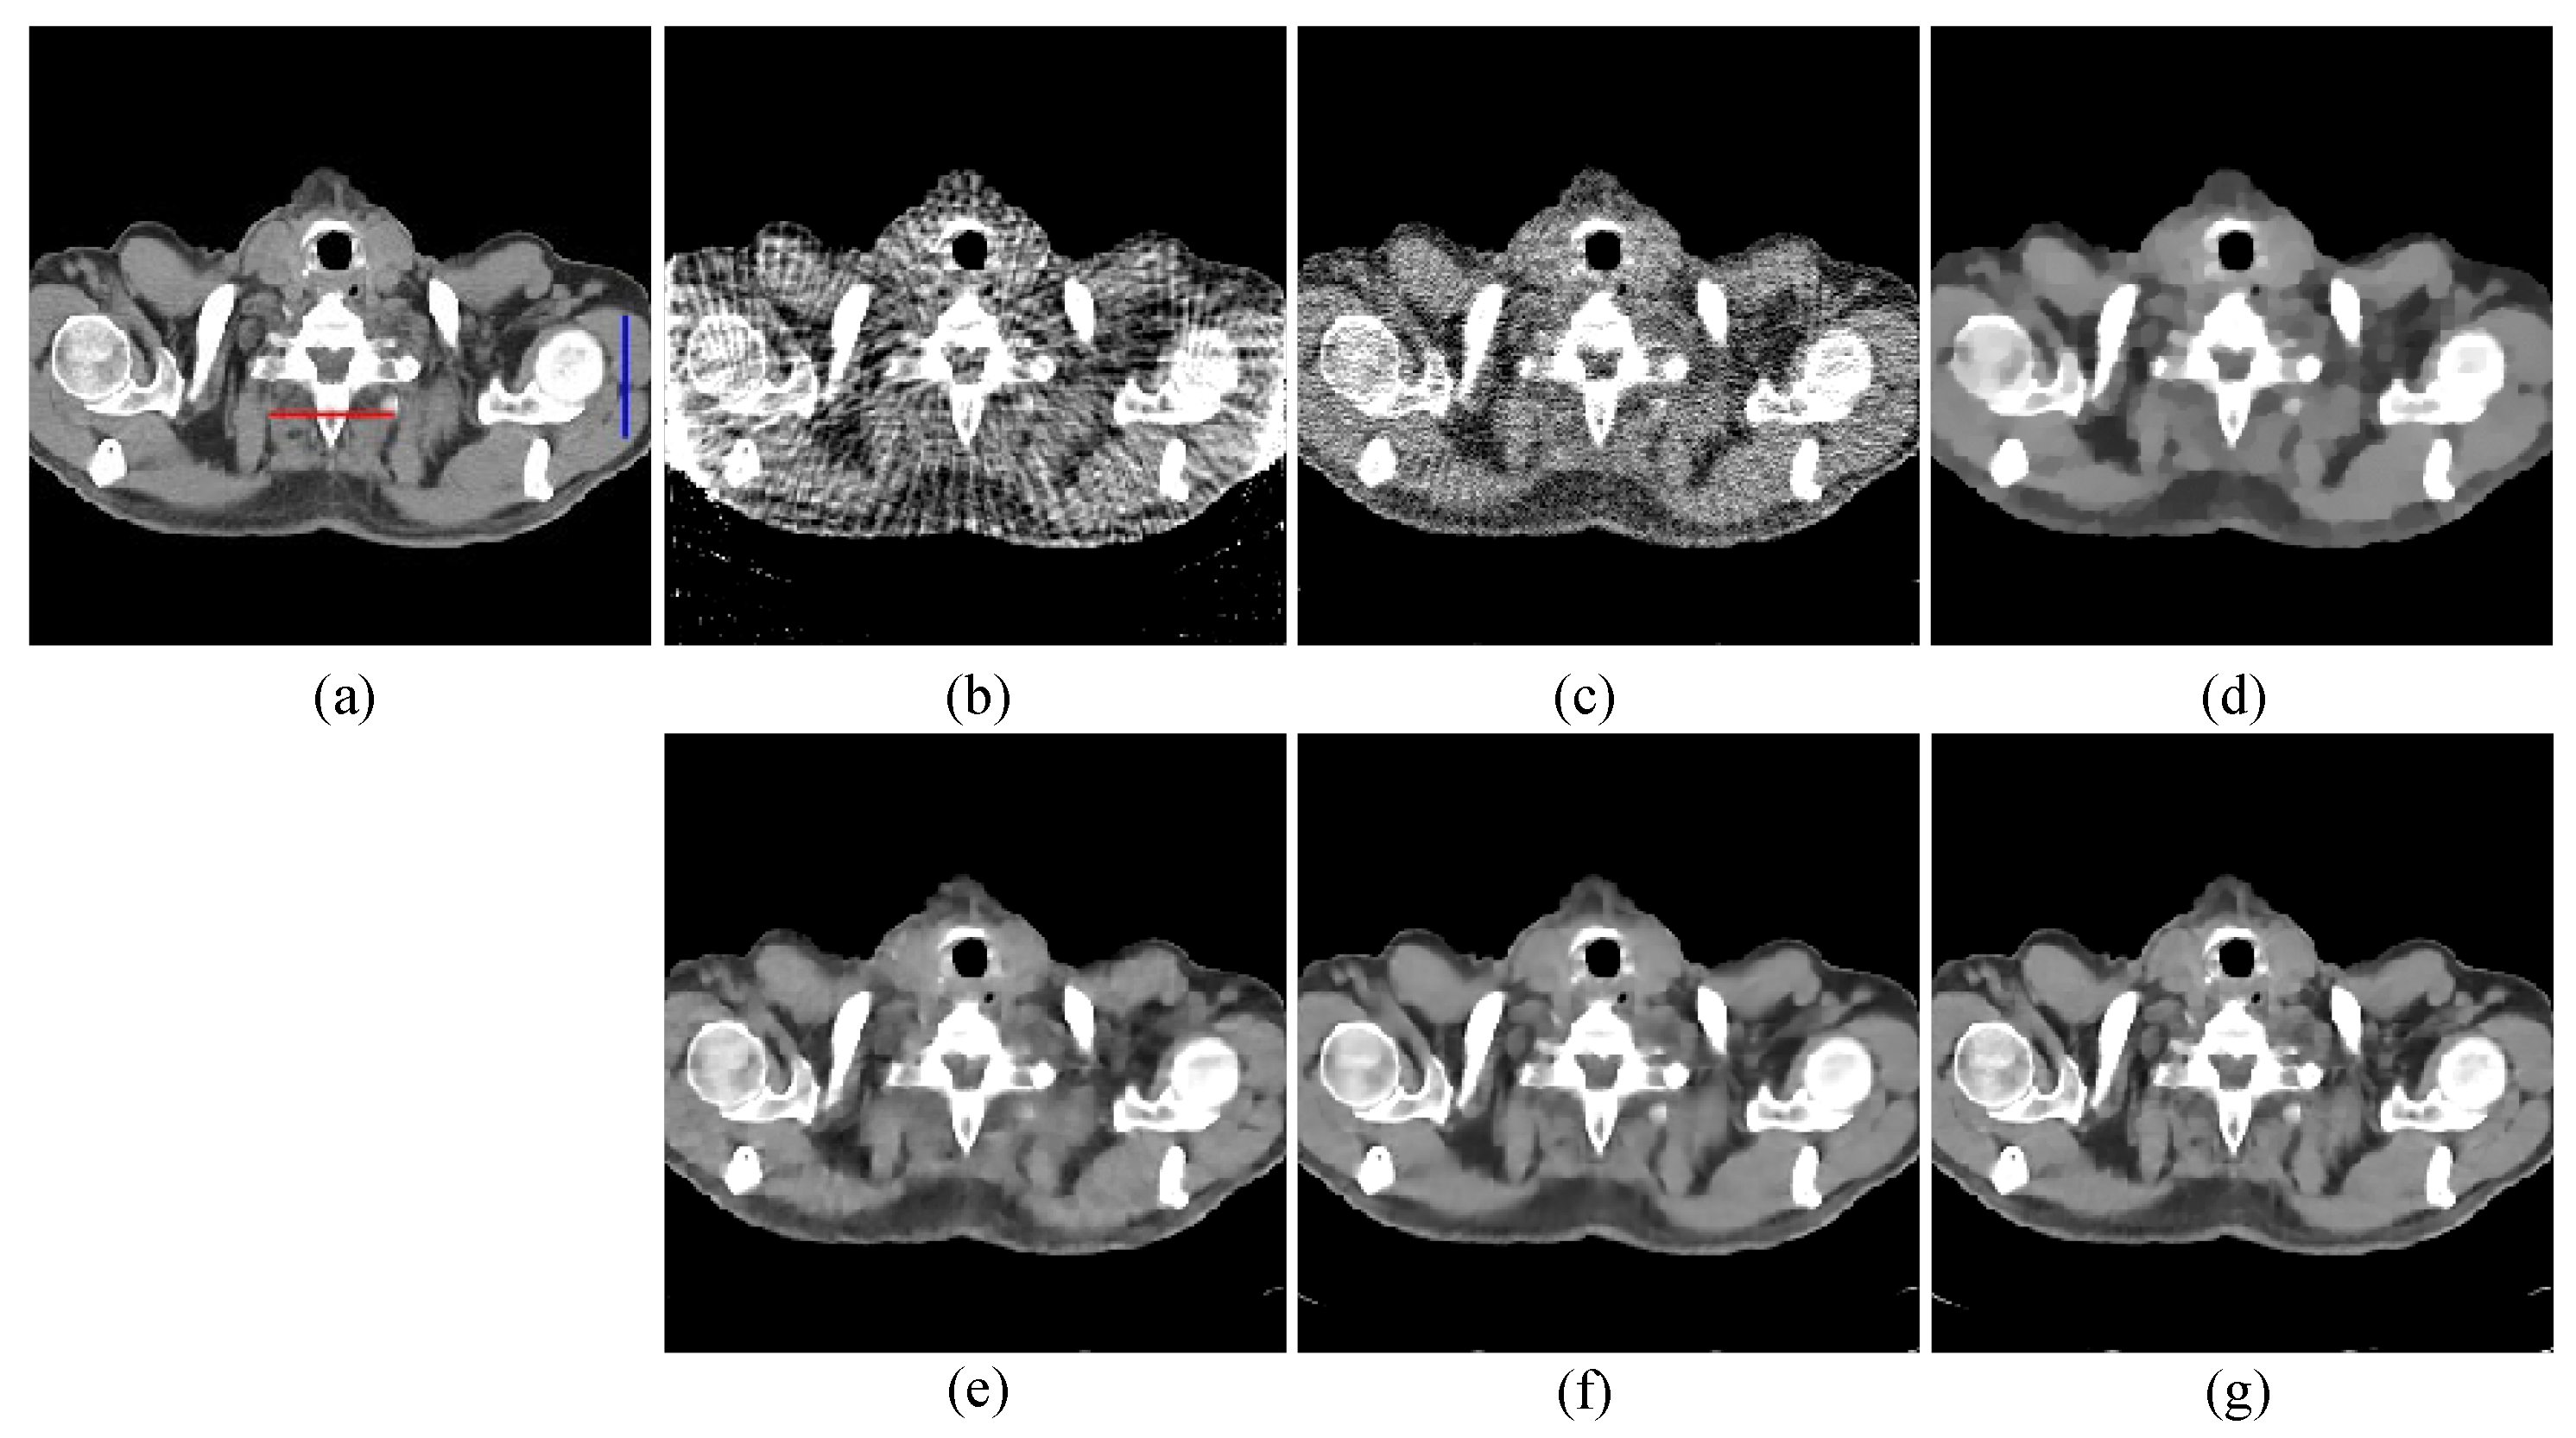

4.1. Image Reconstruction Experiment of Pelvic Image

| Views | 48 | 64 | 80 | |||||||

|---|---|---|---|---|---|---|---|---|---|---|

| Algorithm | RMSE | PSNR | SSIM | RMSE | PSNR | SSIM | RMSE | PSNR | SSIM | |

| FBP | 0.0702 | 23.0708 | 0.4545 | 0.0667 | 23.5219 | 0.5329 | 0.0642 | 23.8551 | 0.5920 | |

| OS-SART | 0.0275 | 31.2206 | 0.7862 | 0.0233 | 31.9316 | 0.8141 | 0.0196 | 32.3883 | 0.8859 | |

| TV | 0.0211 | 32.2309 | 0.8333 | 0.0187 | 32.5749 | 0.8917 | 0.0154 | 35.2963 | 0.9185 | |

| PICCS | 0.0181 | 34.3983 | 0.9016 | 0.0164 | 35.2711 | 0.9132 | 0.0126 | 37.0012 | 0.9329 | |

| TVPI-G | 0.0143 | 35.5365 | 0.9259 | 0.0118 | 37.1833 | 0.9406 | 0.0096 | 38.1127 | 0.9560 | |

| NPICCS | 0.0103 | 37.8746 | 0.9486 | 0.0084 | 39.1328 | 0.9601 | 0.0068 | 40.1574 | 0.9705 | |